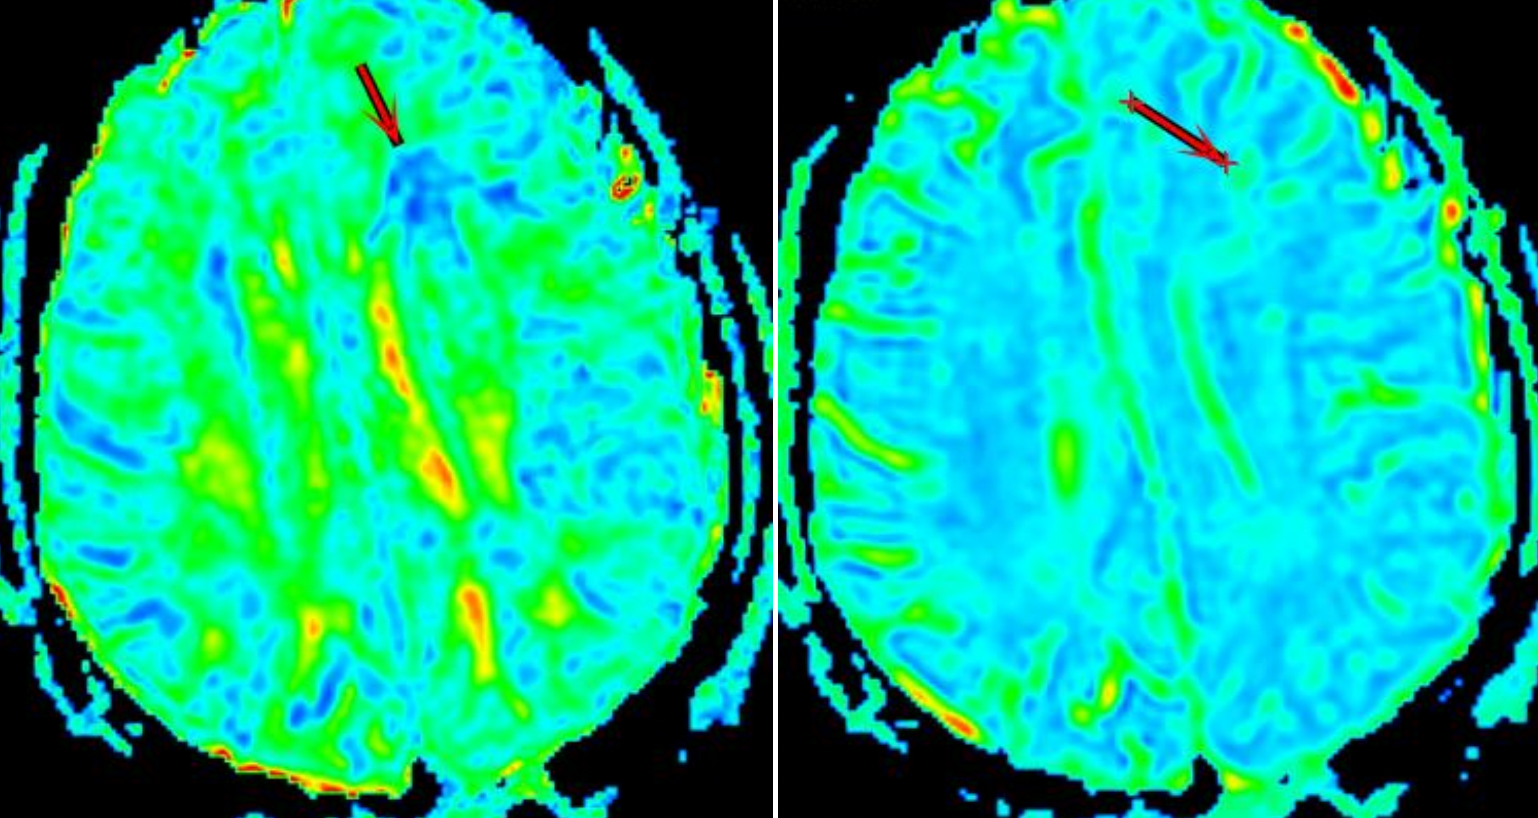

All MRI examinations were conducted on GE signa HDxt1.5T superconducting magnetic resonance scanner. ADW4.6 workstation was used to process the data of the original image. Firstly, routine sequence MRI findings of abnormal brain parenchyma in DAI patients were observed on T1WI, T2WI, FLAIR and DWI images. Then, the Functool software package in the workstation was used to calibrate the DTI and DKI images, and the pseudo-color images of FA,MD and MK values were further reconstructed, as shown in Figure 1A-B. The lesion area of the DAI group and the corresponding layer area of the control group were selected as the region of interest (ROI), and the FA, MD and MK values of the layer were measured. Each ROI was measured three times, and we used the average value. The mean kurtosis (MK), mean diffusivity (MD) and fractional anisotropy (FA) values of the two groups were measured. Two independent sample T tests were used to analyze the MK, MD and FA values of the two groups. The sensitivity, specificity and accuracy of each parameter were analyzed to evaluate the diagnostic efficiency of DAI.

Fig1